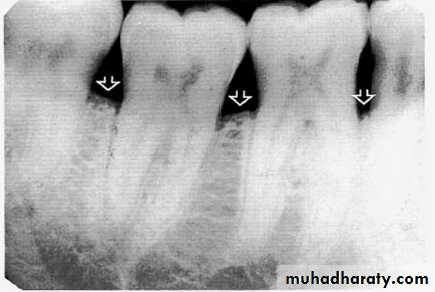

Bone loss

• Severity: classified to

Mild bone loss: crestal changes (The anterior regions show blunting of the alveolar crests and slight loss of alveolar bone height.Posteriorly show loss of the normally sharp angle between the lamina dura and alveolar crest).

• Moderate bone loss: bone loss of 10-33%.

• Severe bone loss: bone loss of 33% or more.

Mild bone loss